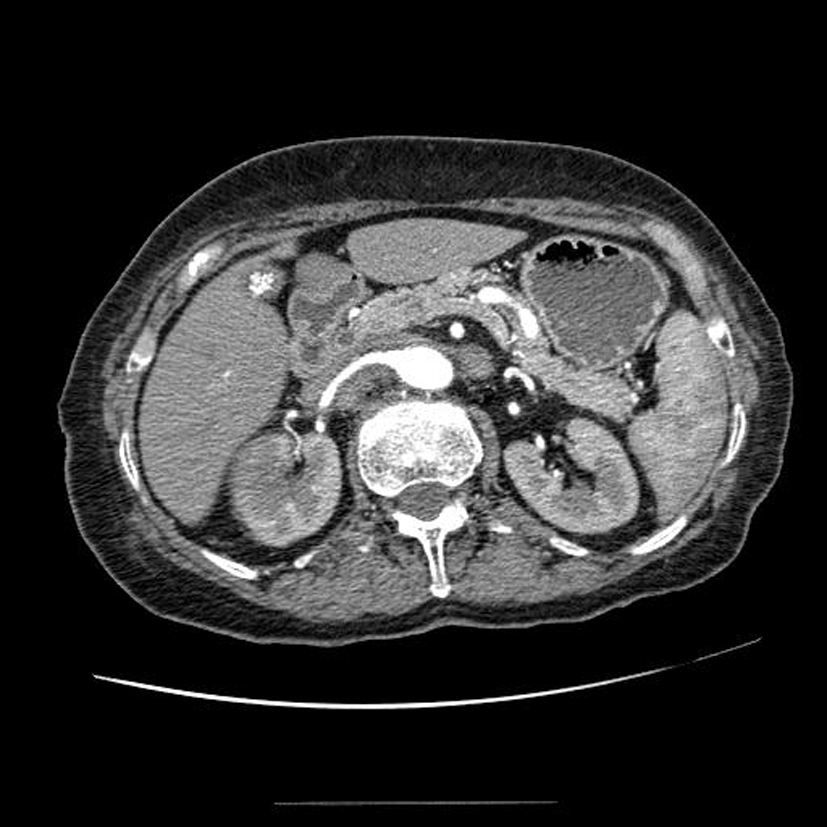

Diagnostic?

Tumeur rénale droite avec adénopathies au niveau du pédicule rénal